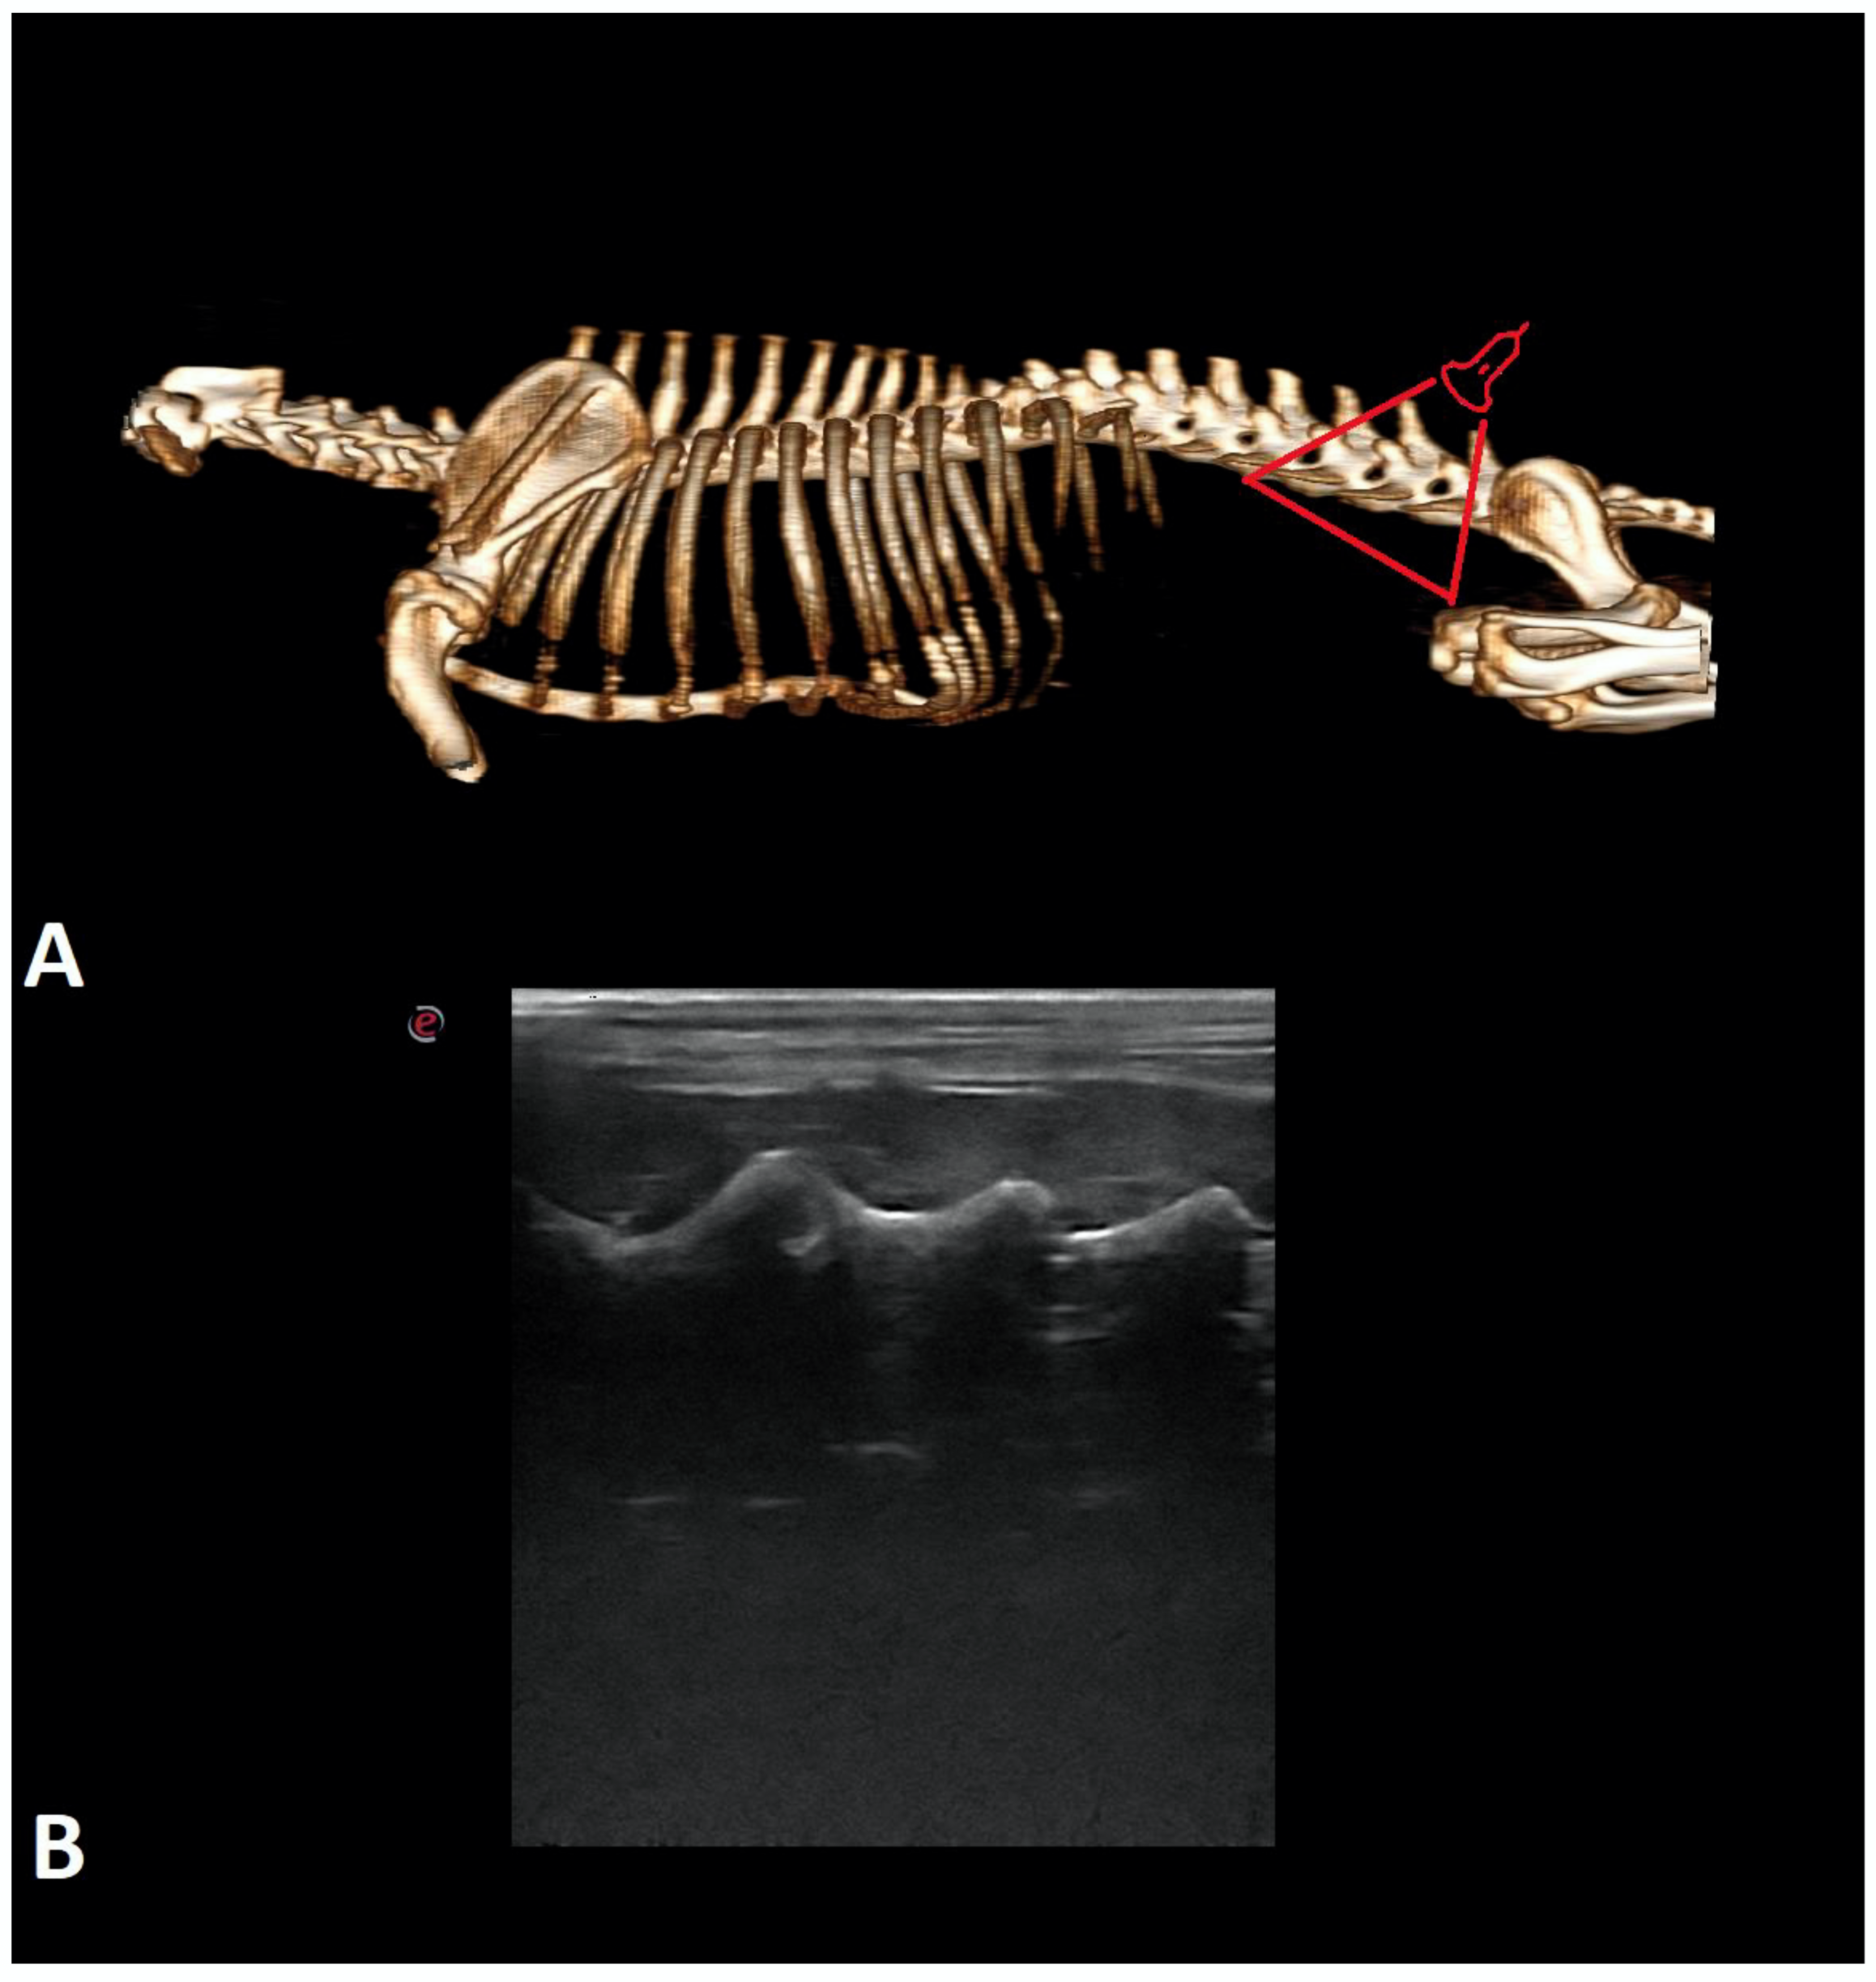

- Lopes, É.R.; Bellegard, G.M.; Cury, F.S.; Abreu, F.A.; Ambrósio, C.E.; Carregaro, A.B.; Hage, M.C.F. Evaluation of the applicability of musculoskeletal ultrasonography of the thoracolumbar and lumbar spine segment of healthy dogs. Pesqui. Veterinária Bras. 2018, 38, 2278–2283. [Google Scholar] [CrossRef]